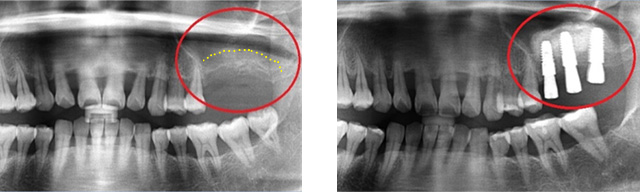

아래턱 어금니 발치 후 장시간 방치하여 잇몸 뼈 소실이 심한 상태로 내원. 뼈 이식 후 임프란트를 식립하였습니다.

잇몸 뼈 소실이 심한 상태로 내원

뼈 이식 후 치조골 밀도가 높아진 모습